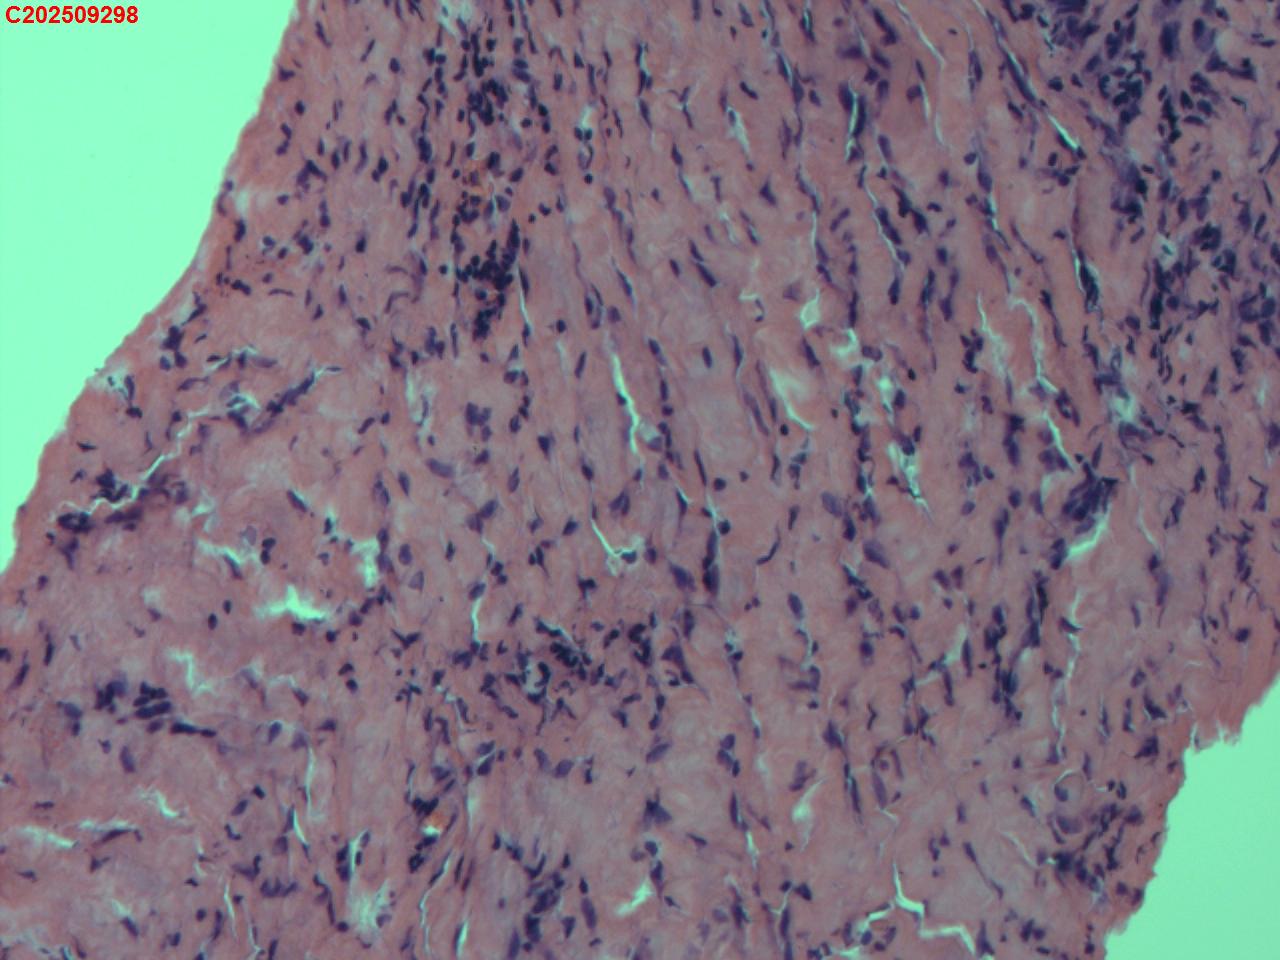

性别

女

年龄

34岁

临床诊断

胸膜结核瘤

一般病史

超声:可见右侧胸膜包裹囊性病变并见胸膜结核瘤。

标本名称

肺穿活检

大体所见

CT:胸部增强CT示右肺病灶局部增大,右侧胸腔结核性胸膜瘤可能。

送检组织·,镜下为炎性细胞和纤维组织。